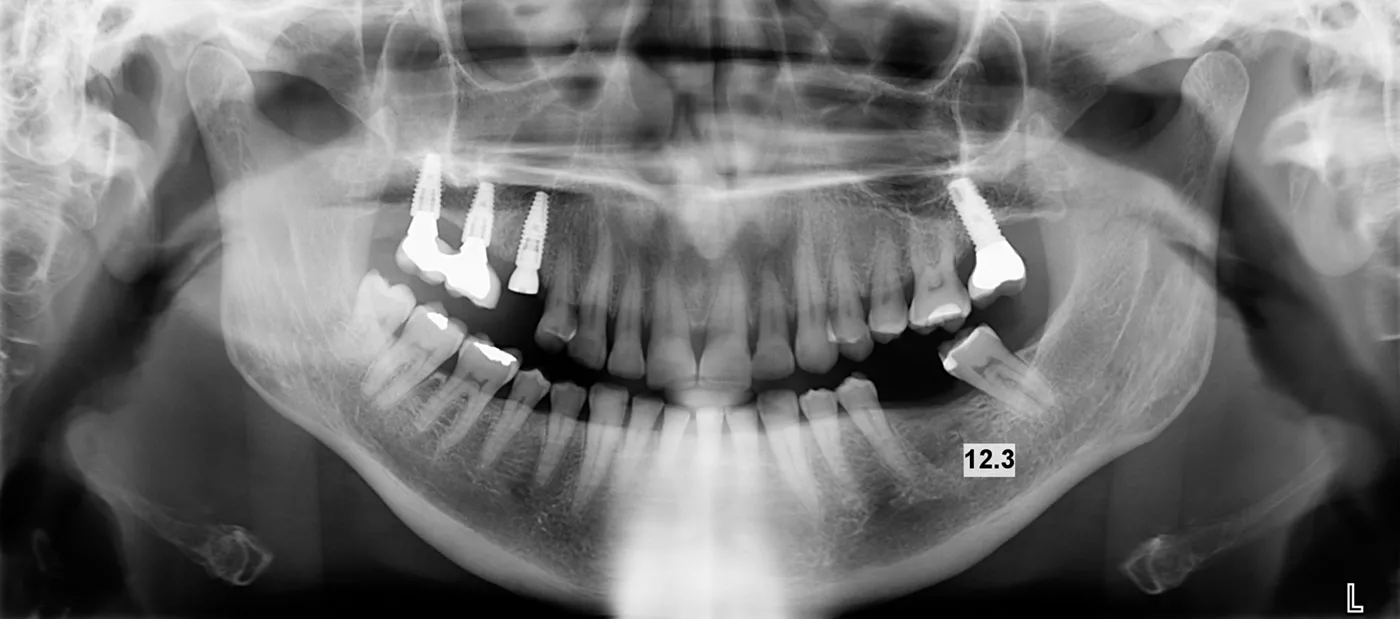

Two months later, a panoramic x-ray showed an excellent situation for the BLT implant and correct healing of the #36 area (Fig. 1).

fig. 1